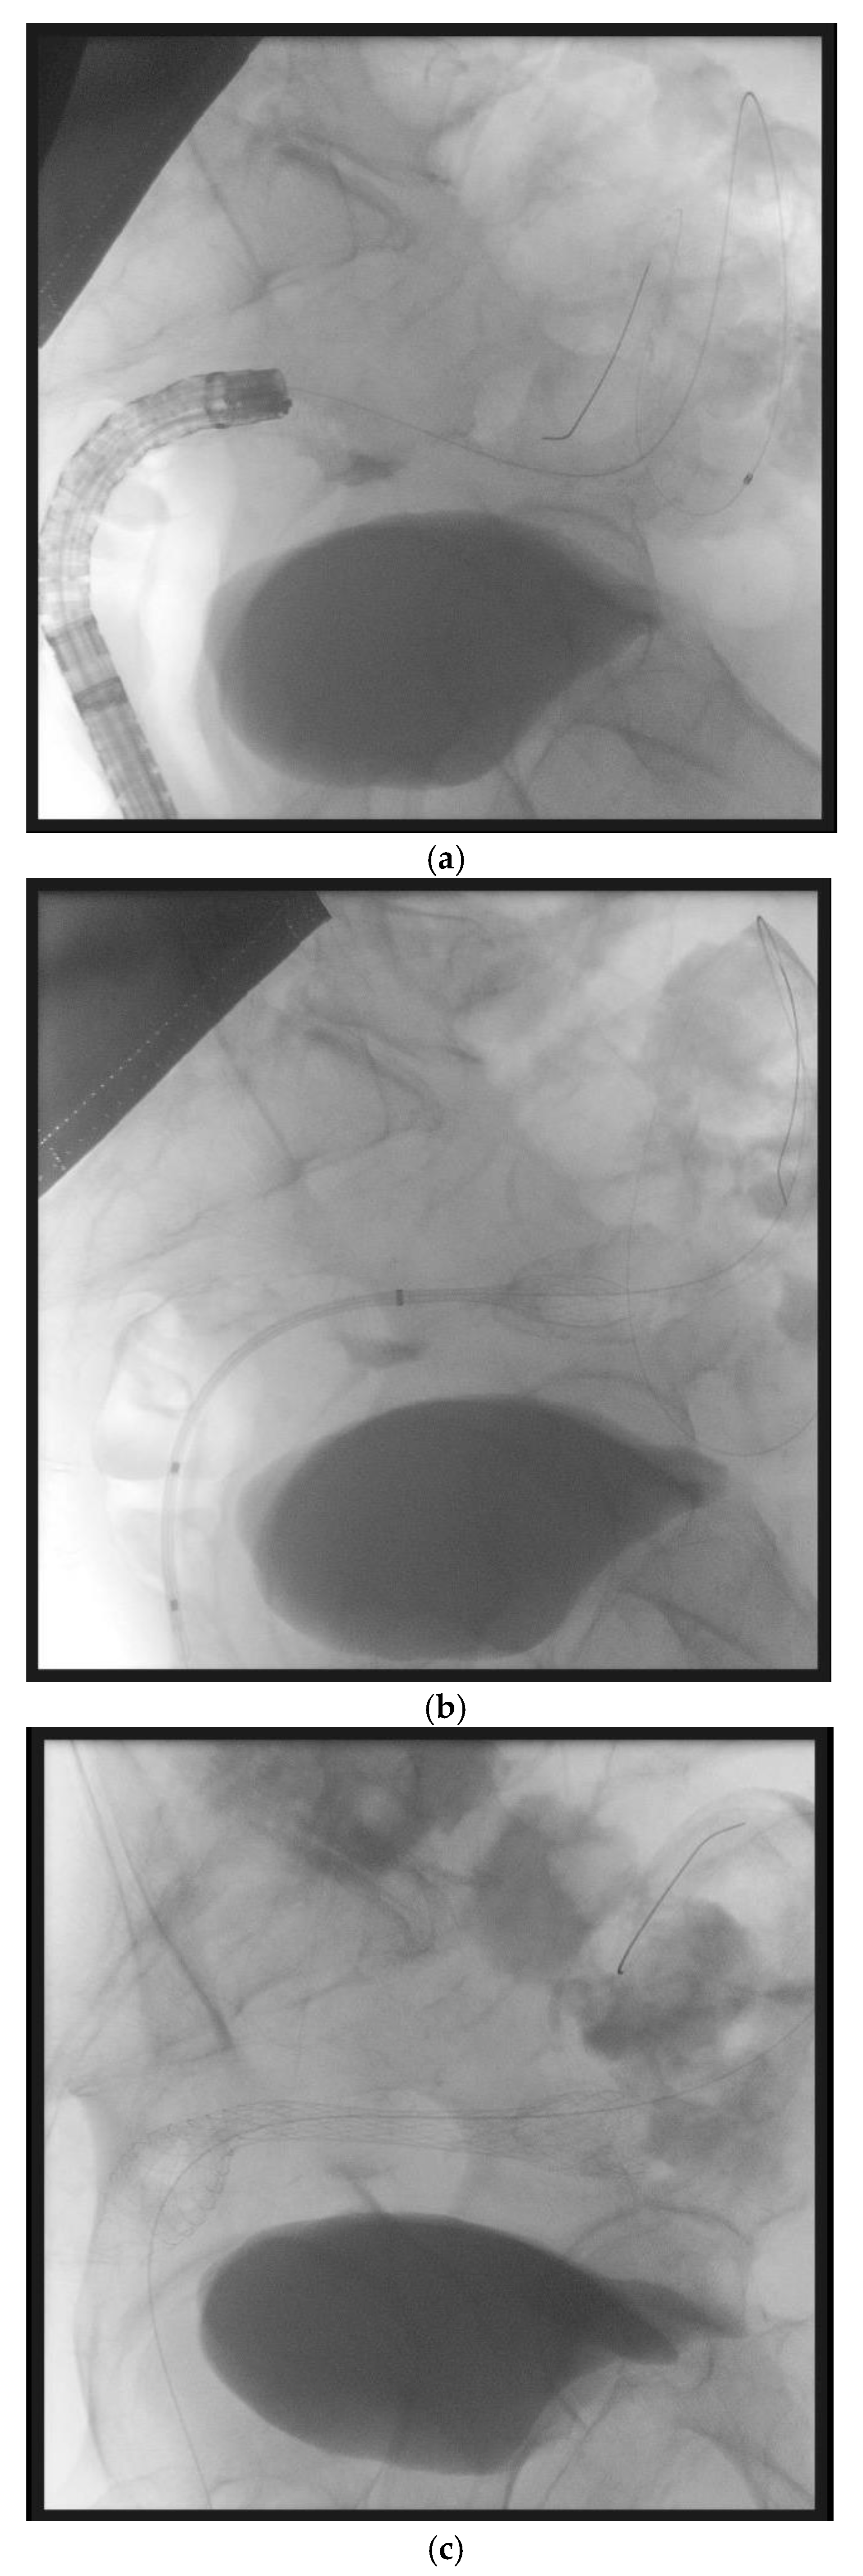

10. Endoscopic Ultrasound-Guided Entero-Colostomy with LAMS